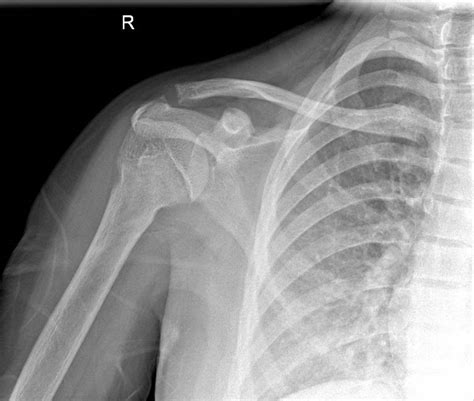

Interpreting a Shoulder Xray Normal

When a radiologist reviews a shoulder X-ray, they look for specific features that indicate a normal shoulder joint. These features include:

• Alignment of Bones: The humeral head should be properly aligned with the glenoid fossa of the scapula.

• Bone Density: The bones should have a uniform density without any areas of increased or decreased density.

• Joint Spaces: The joint spaces should be uniform and without any narrowing or irregularities.

• Soft Tissues: The soft tissues around the joint should appear normal without any swelling or abnormalities.

If all these features are present, the X-ray is considered Shoulder Xray Normal.

Common Findings in a Shoulder Xray Normal

A normal shoulder X-ray typically reveals the following:

• Humeral Head: The head of the humerus should be round and well-defined, sitting snugly in the glenoid fossa.

• Glenoid Fossa: The glenoid fossa should be smooth and without any erosions or irregularities.

• Acromioclavicular Joint: This joint should be well-aligned and without any signs of separation or dislocation.

• Clavicle: The clavicle should be intact and without any fractures or deformities.

• Soft Tissues: The soft tissues around the shoulder should appear normal, with no signs of swelling or inflammation.